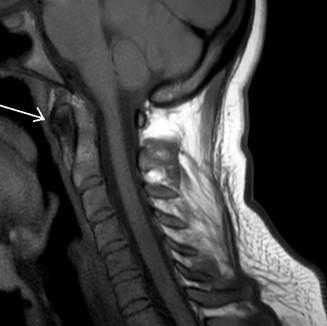

При наличии дегенеративных изменений определяли частоту, приблизительный возраст наступления и степень изменений, проводили сверку с общей статистикой дегенеративных изменений в атланто-аксиальных суставах. Произведены сравнительная анатомия конфигурации частей атланта и осевого позвонка в основной и контрольной группах, измерение сагиттальных размеров толщины передней дужки атланта на различной удаленности от медианы (переднего бугорка). Измеряли переднезадние и вертикальные размеры сечения в сагиттальной плоскости, отступив на 2 мм от медианы латерально (рис. 3).

Рис. 3. Сагиттальные томограмммы Т1 и Т2ВИ (красный контур сагиттальной плоскости сечения расщепленной передней дужки атланта)